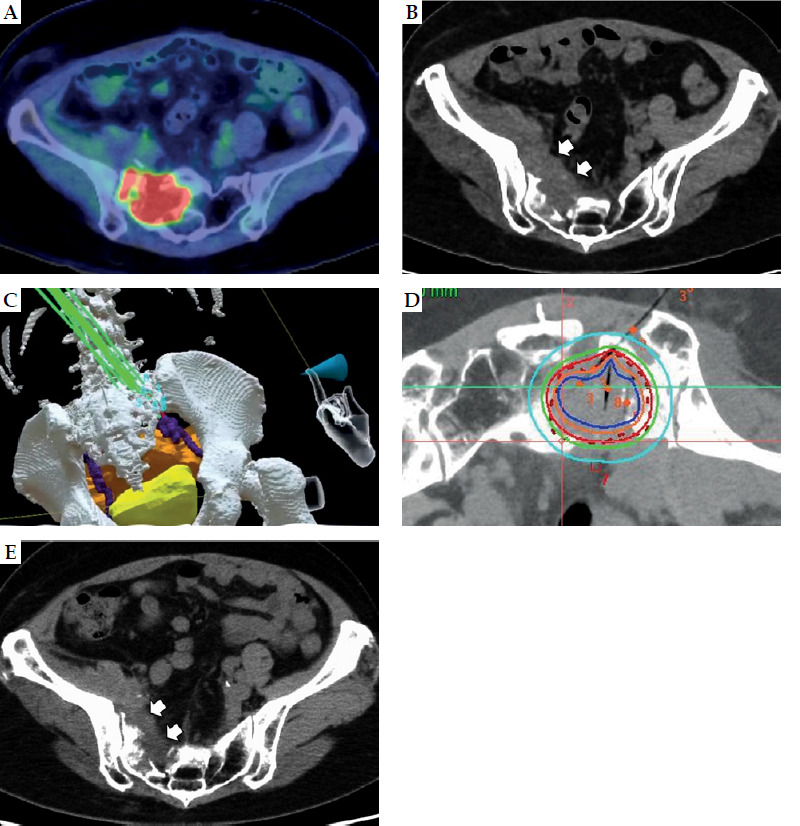

Cases description: Case 1: A 51-year-old woman with carcinoma of unknown primary and poorly differentiated adenocarcinoma had previously undergone chemotherapy and radiation therapy for a large tumor in the right common iliac region. The tumor recurred and invaded the sacrum, requiring interstitial brachytherapy due to prior radiation dose constraints. Applicator placement was challenging, necessitating collaboration with an interventional radiology (IR) physician. VR pre-simulation facilitated multi-disciplinary communication and optimized puncture, leading to a safer and more accurate procedure. Case 2: A 46-year-old man with floor of the mouth cancer was initially scheduled for total glossectomy and laryngectomy, but opted for radiotherapy after significant tumor shrinkage. To minimize radiation dose to the mandible, interstitial brachytherapy was added. Due to safety concerns regarding prolonged applicator placement, a strategy of daily insertion and removal was adopted. A custom-made mouthpiece with a single guiding applicator was prepared by a dentist, and multiple needle-type applicators were employed. VR pre-simulation enabled precise needle insertion and facilitated procedural consistency, even among radiation oncologists unfamiliar with head and neck brachytherapy.